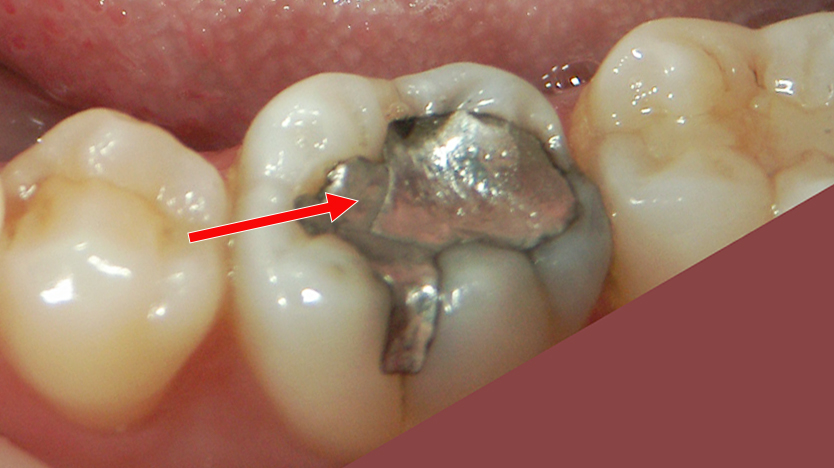

二次カリエスを起こしたアマルガム充填症例

画像は右下第1大臼歯(6番)の頬側面を示しています。矢印で示された部位にアマルガム充填が施されています。アマルガムは銀色の金属充填材で、かつて虫歯治療によく使われていました。

充填部の周囲に黒ずみ(変色)や境界のわずかな段差が見られ、充填の劣化や**二次カリエス(二次う蝕)**の可能性が高い状態です。これは、充填材と歯質の間にわずかな隙間が生じ、そこに細菌が侵入して再び虫歯が発生するケースです。

解説まとめ

- 部位:右下第1大臼歯(6番)頬側

- 処置歴:アマルガム充填(旧来の金属修復)

- 現状:充填境界部に変色と隙間 → 二次カリエス疑い

- リスク:虫歯の進行による象牙質・神経への感染リスク

- 推奨治療:古いアマルガムの除去後、う蝕除去を行い、コンポジットレジン(白い樹脂)による再修復が望ましいです。

審美面・健康面の両方から、早めの再治療が推奨される症例です。